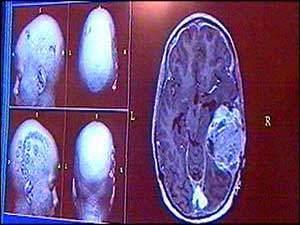

نجح علماء من سويسرا وبريطانيا في تطوير "سلاح موجه" جديد من نوعه قادر على تدمير الأورام الخبيثة في الجلد لدى فئران المختبر.واستخدم الباحثون أجساماً مضادة لجعل جزيئات بروتينية حساسة للضوء تلتصق بشكل هادف بالأوعية الدموية في المنطقة المصابة بالورم الخبيث مما جعل هذه الجزيئات تمنع وصول الدم لهذه الأورام عندما يتم تفعيلها بالضوء، حسبما أوضح الباحثون في مجلة "بريتيش جورنال أوف ساينس" البريطانية المتخصصة.

غير أن الباحثين شددوا على أن الوقت لا يزال طويلاً أمام تطوير جزيئات بروتينية من نوع جديد مضادة للسرطان لدى الإنسان غير أنهم أكدوا في الوقت ذاته أن الدراسة تفتح الطريق أمام تطوير طرق علاجية جديدة من السرطان.

وليست استراتيجية قطع الدم عن الورم الخبيث جديدة بين العلماء، حيث أن هناك بالفعل عقاقير تستخدم لدى مرضى السرطان لهذا الغرض. غير أن الباحثين يأملون في جعل هذه الطريقة أكثر فعالية من خلال ربطها بأجسام مضادة يتم توجيهها بشكل هادف لتلتصق بالأوعية الدموية للورم السرطاني وذلك لخفض الجرعة العلاجية من هذه العقاقير مما يؤدي إلى خفض المضاعفات الجانبية لها.

وأكد الباحثون أنهم نجحوا في إلصاق جزيئات بروتينية بأجسام مضادة أنتجت جذورا أكسيجينية عند تفعيلها باستخدام الضوء. ونجحت هذه الجذور في تدمير الخلايا السرطانية الموجودة في الأوعية الدموية مما أدى إلى موت الخلايا السرطانية جوعاً.

كما أكد الباحثون أن هذه الطريقة العلاجية أدت إلى اختفاء بعض الأورام السرطانية في الجلد بشكل تام وأدت إلى منع نشأة تورمات خبيثة أخرى خلال المئة يوم التالية.

غير أن الباحثين من جامعة زيوريخ الوطنية للعلوم التطبيقية شددوا في الوقت ذاته على أن هذه الطريقة العلاجية تعمل بمساعدة الجهاز المناعي للجسم وأن هذه الطريقة أدت إلى تقلص الأورام السرطانية فقط ولم تؤد لاختفائه وذلك عندما أوقفوا الجهاز المناعي لدى الفئران.

ويعتزم الباحثون الوقوف على السبب وراء ذلك من خلال دراسات أخرى آملين بهذه الطريقة في تحسين طرق التداوي من السرطان "فهذه الدراسة تمهد لنا الطريق لتطوير نوعية جديدة من الأساليب العلاجية القائمة على استخدام الأجسام المضادة" حسبما أوضح داريو نيري الذي أشرف على فريق الباحثين السويسريين.